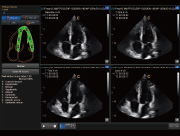

四维,断层成像

负荷心超